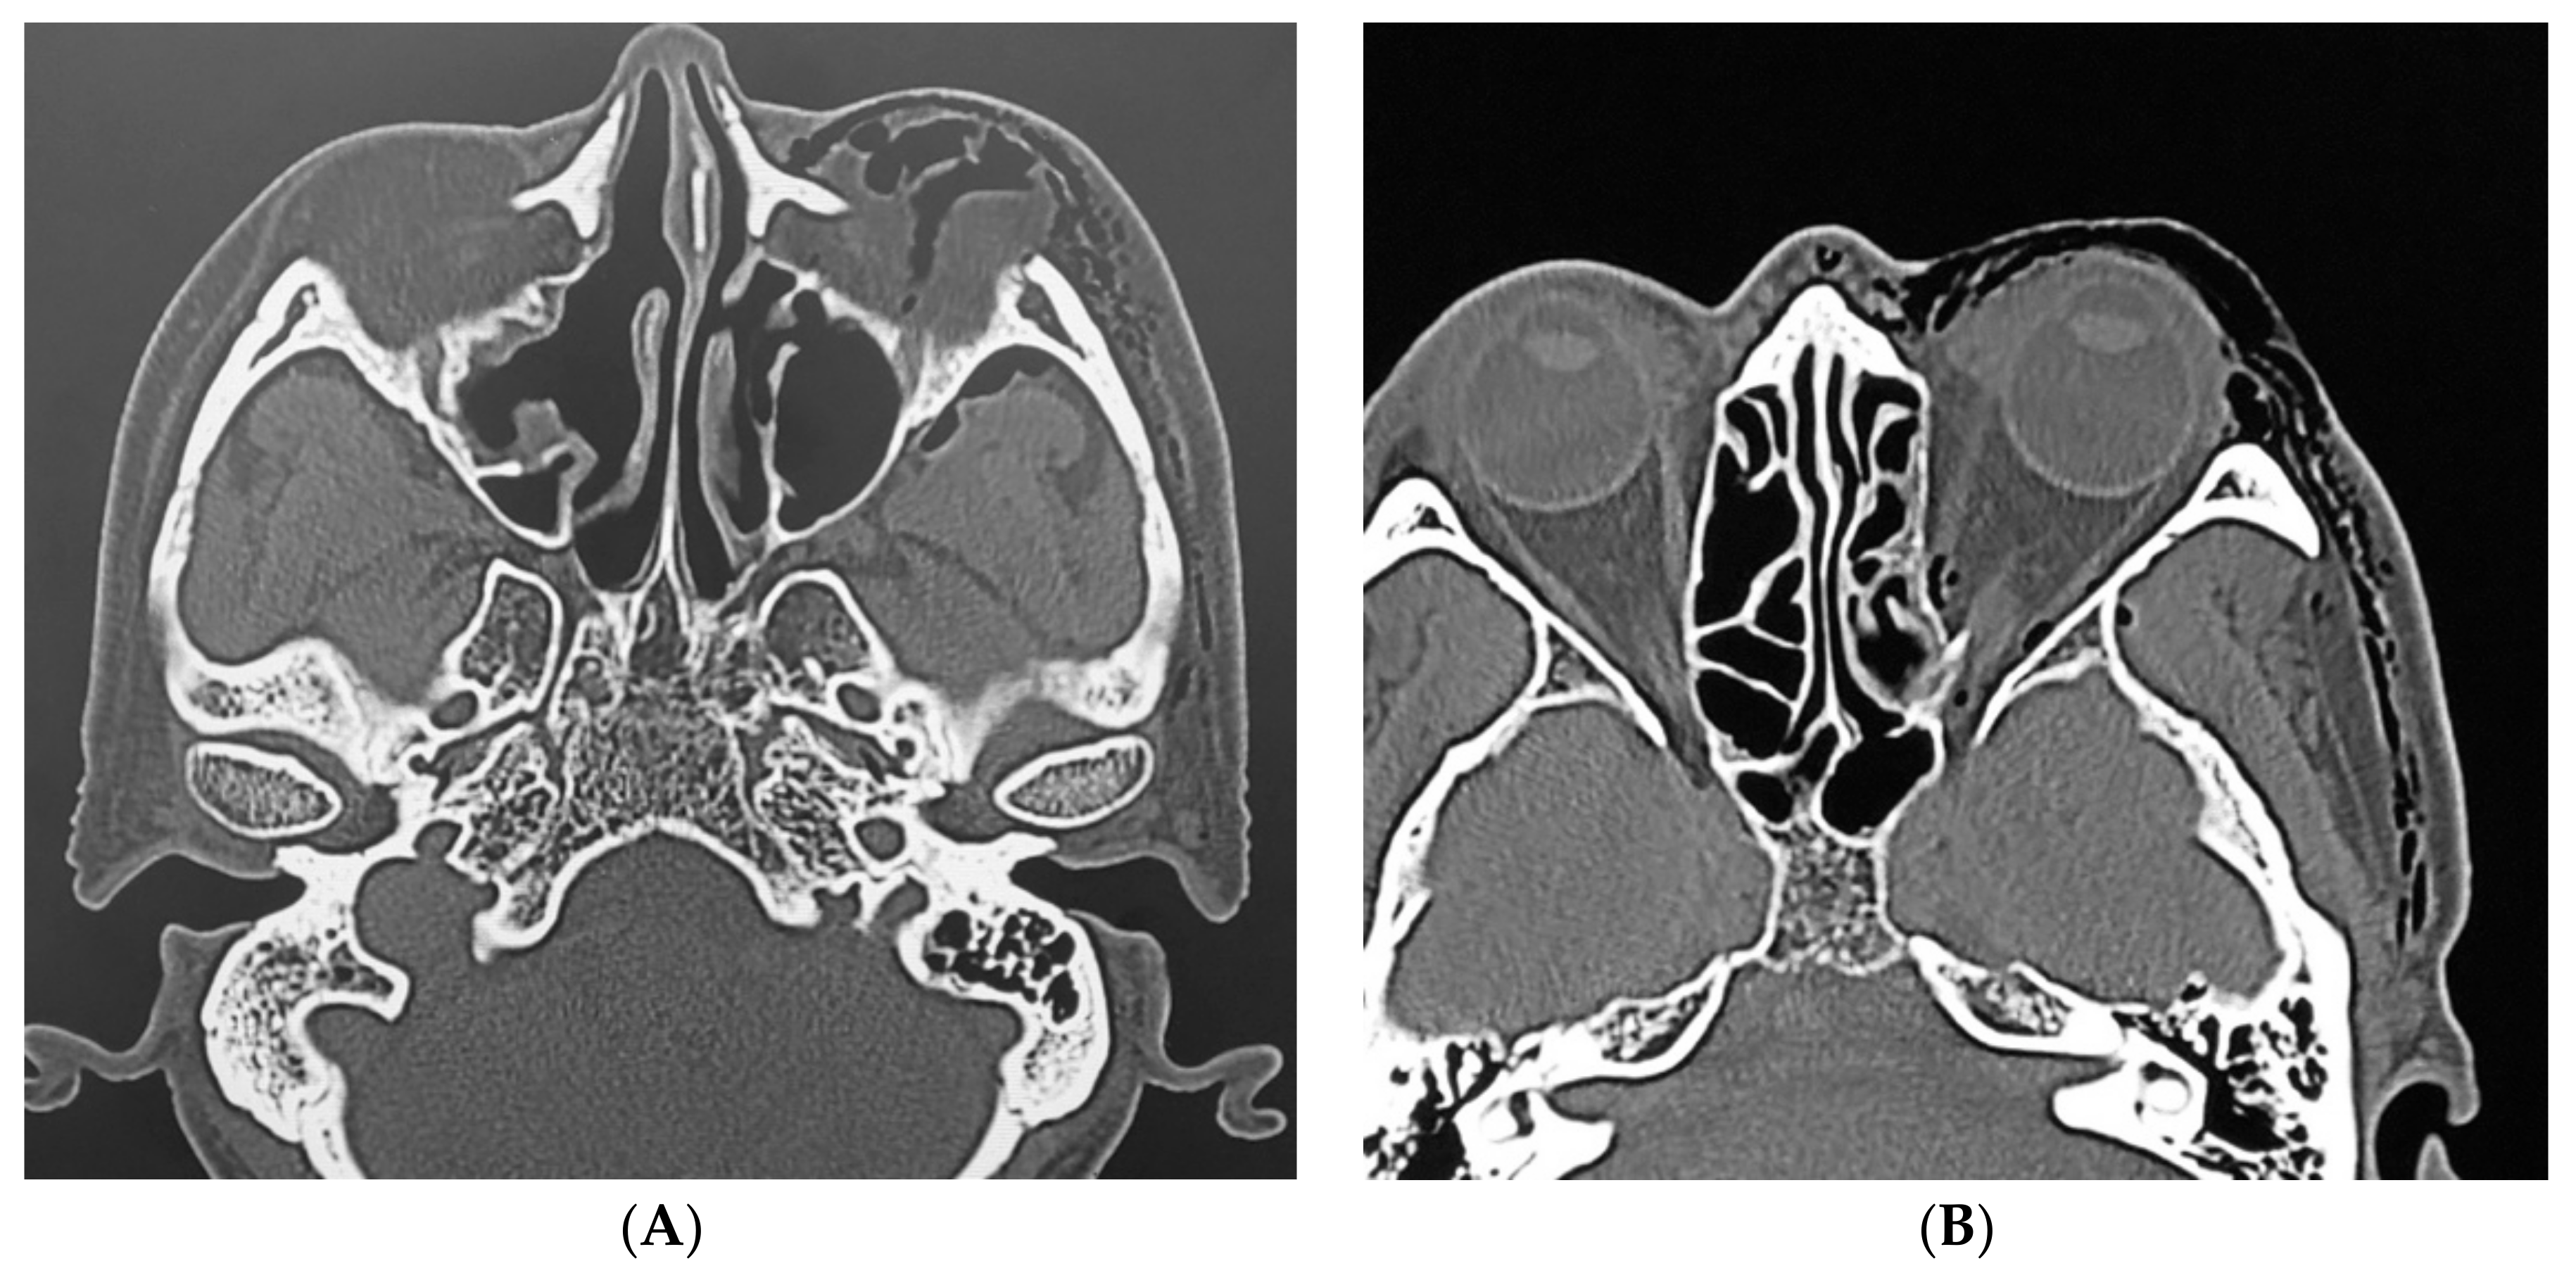

Subcutaneous Emphysema of the Orbit after Nose-Blowing

2. Case Description